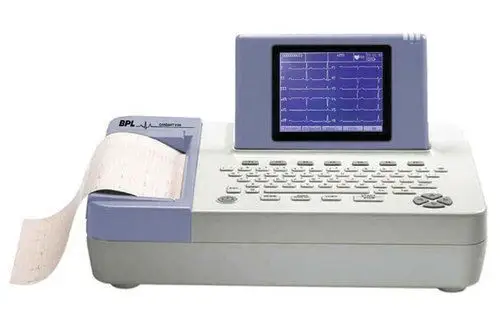

Diagnostic Tests

Including ECG, 2D Echo & Color Doppler, TMT (Stress Test), 24-hour Holter Monitoring, and ABPМ.